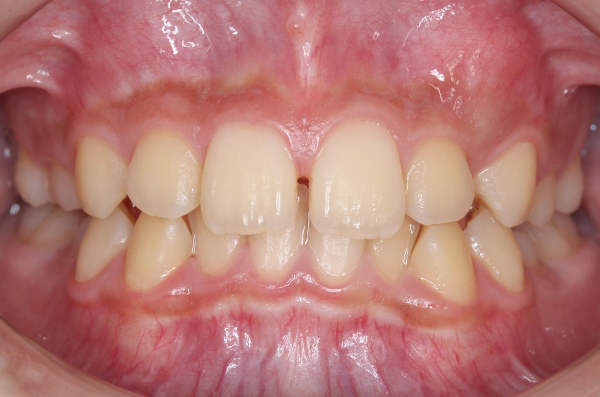

成長発育の口腔内変化

個々人でお口の中の成長発育は異なります。発育の変化の一例を掲載いたします。このように、永久歯に生え変わる前の写真があると、その後の成長発育の変化と比較ができます。

※画像クリックで拡大表示。